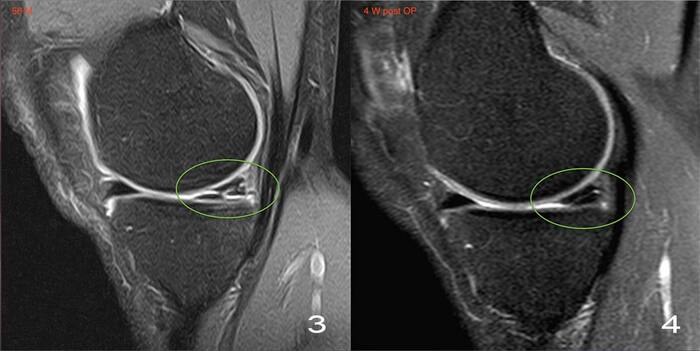

МРТ, когда нужно заглянуть дальше, например, чтобы исключить повреждение заднего рога мениска или крестообразных связок - такие глубоко залегающие структуры по УЗИ не видно.

Иногда в полости кисты можно найти какие-нибудь образования, которые мигрировали из полости сустава (кальцинаты, костные тела, хрящевые тела, костно-хрящевые).

травмы - повреждение менисков (чаще задний рог медиального мениска), разрывы передней крестообразной связки.